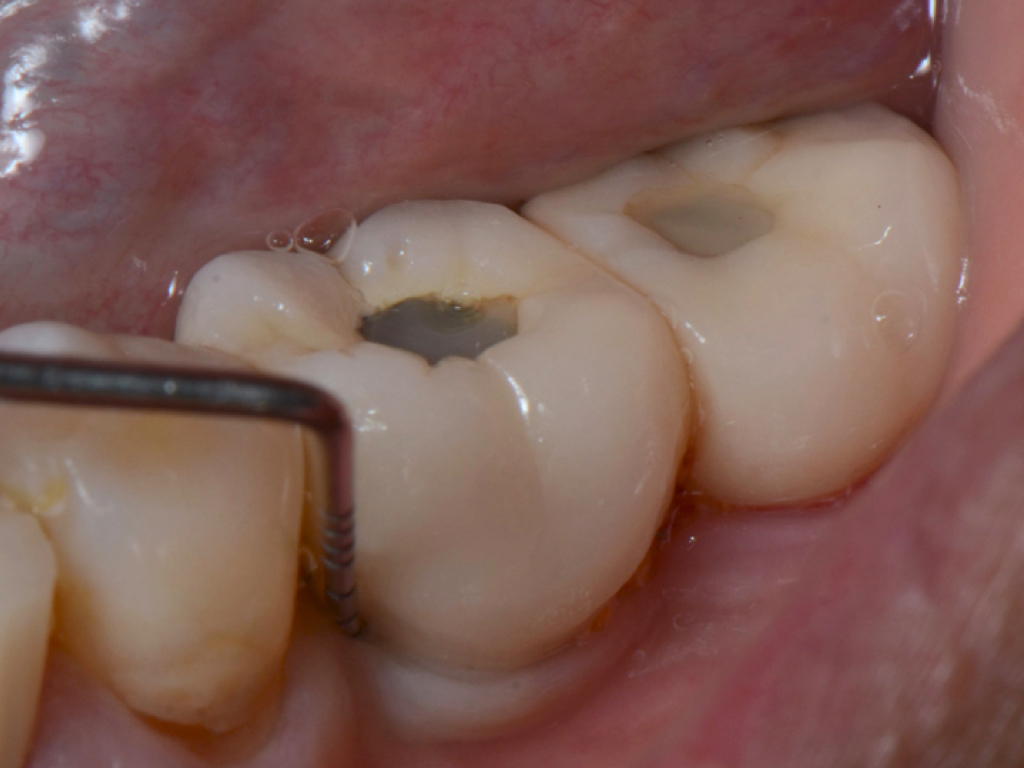

Fig 1. Inaccurate probing angle wrongly indicates probing depth at 3 mm, which does not correspond to the radiographic finding shown in Fig 2.

Figure 1

Fig 3. Correct angulation of the probe demonstrates 6-mm probing depth.

Figure 3

Clinical PPD is measured to the nearest millimeter by means of a graduated periodontal probe with a standardized tip diameter of approximately 0.4 mm to 0.5 mm. Several factors can influence the measurements made with periodontal probes, including: the thickness of the probe used5; the angulation and positioning of the probe depending on anatomic features, such as the contour of the tooth surface (Figure 1 through Figure 3)6; the graduation scale of the probe5; the pressure applied on the instrument during probing6; and the degree of inflammatory cell infiltration in the soft tissue and accompanying loss of collagen.7